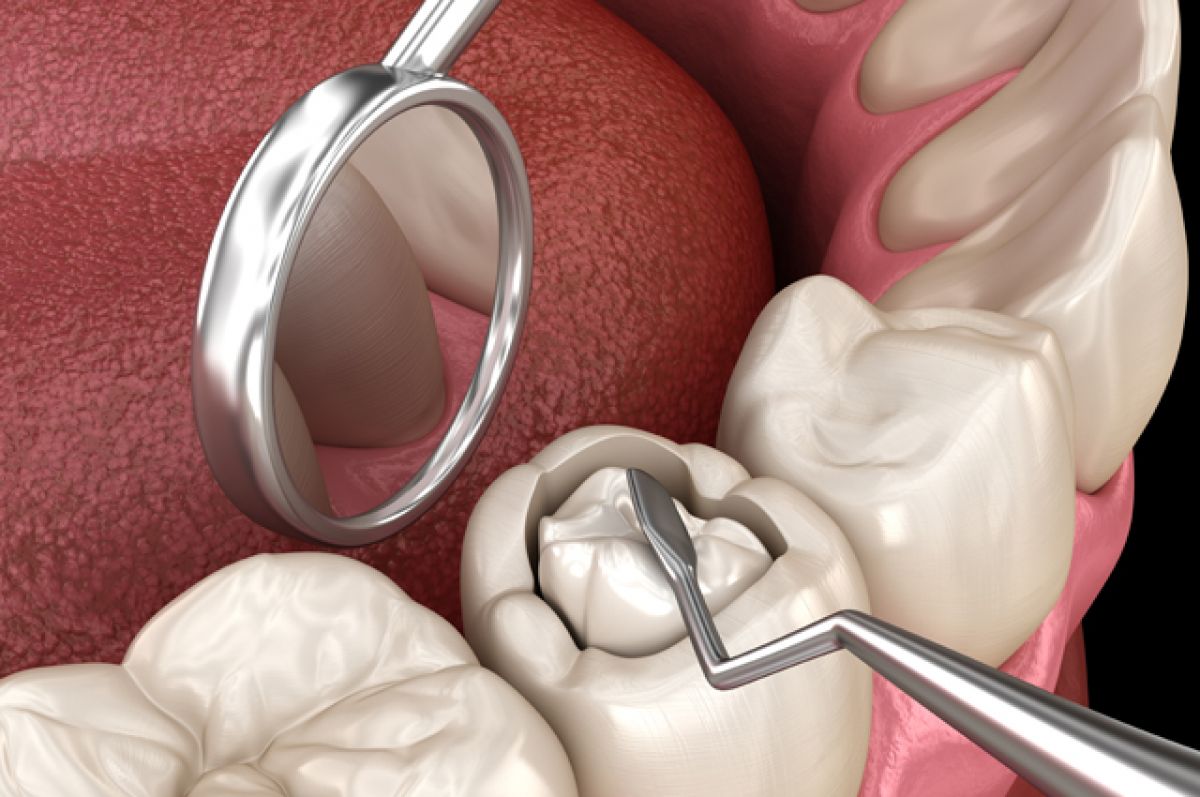

Restoration of Decayed Teeth

At Smile Dental Clinic and Implant Centre, we restore decayed teeth with treatments like fillings, crowns, and root canals to keep your smile healthy and strong.

Filling

A Dental Filling is a treatment used to restore the function, integrity, and morphology of missing tooth structure caused by decay or trauma. The process involves removing decayed tooth material, cleaning the affected area, and then filling the cavity with a restorative material. Tooth-colored resin.